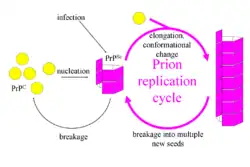

The first hypothesis that tried to explain how prions replicate in a protein-only manner was the heterodimer model.[60] This model assumed that a single PrPSc molecule binds to a single PrPC molecule and catalyzes its conversion into PrPSc. The two PrPSc molecules then come apart and can go on to convert more PrPC. However, a model of prion replication must explain both how prions propagate, and why their spontaneous appearance is so rare. Manfred Eigen showed that the heterodimer model requires PrPSc to be an extraordinarily effective catalyst, increasing the rate of the conversion reaction by a factor of around 1015.[61] This problem does not arise if PrPSc exists only in aggregated forms such as amyloid, where cooperativity may act as a barrier to spontaneous conversion. What is more, despite considerable effort, infectious monomeric PrPSc has never been isolated.[62]

An alternative model assumes that PrPSc exists only as fibrils, and that fibril ends bind PrPC and convert it into PrPSc. If this were all, then the quantity of prions would increase linearly, forming ever longer fibrils. But exponential growth of both PrPSc and the quantity of infectious particles is observed during prion disease.[63][64][65] This can be explained by taking into account fibril breakage.[66] A mathematical solution for the exponential growth rate resulting from the combination of fibril growth and fibril breakage has been found.[67] The exponential growth rate depends largely on the square root of the PrPC concentration.[67] The incubation period is determined by the exponential growth rate, and in vivo data on prion diseases in transgenic mice match this prediction.[67] The same square root dependence is also seen in vitro in experiments with a variety of different amyloid proteins.[68]

The mechanism of prion replication has implications for designing drugs. Since the incubation period of prion diseases is so long, an effective drug does not need to eliminate all prions, but simply needs to slow down the rate of exponential growth. Models predict that the most effective way to achieve this, using a drug with the lowest possible dose, is to find a drug that binds to fibril ends and blocks them from growing any further.[69]

Proteins showing prion-type behavior are also found in some fungi, which has been useful in helping to understand mammalian prions. Fungal prions do not always cause disease in their hosts.[120] In yeast, protein refolding to the prion configuration is assisted by chaperone proteins such as Hsp104.[121] All known prions induce the formation of an amyloid fold, in which the protein polymerises into an aggregate consisting of tightly packed beta sheets. Amyloid aggregates are fibrils, growing at their ends, and they replicate when breakage causes two growing ends to become four growing ends. The incubation period of prion diseases is determined by the exponential growth rate associated with prion replication, which is a balance between the linear growth and the breakage of aggregates.[67]